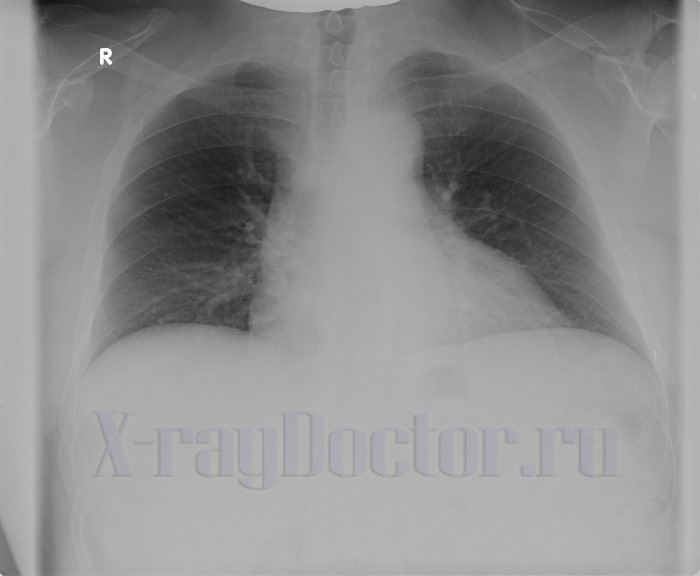

Итак, возьмем рентгеновский снимок легких и попробуем отличить нормальные анатомические структуры от патологических.

Норма на рентгене грудной клетки:

- черные легочные поля (симметрично с обеих сторон);

- белая тень посередине (сердце)

- серая костная структура (ребра, плечевые суставы);

- белые дугообразные «купола» (снизу под легочными полями, симметрично);

- позвоночный столб посередине.

Как обнаружить патологию на рентгенограмме:

- дополнительные белые тени на фоне легочных полей;

- увеличение ширины или деформация контуров нормальных анатомических структур (грудины, сердца, позвоночника);

- кольцевидные полости в легочных полях;

- белые горизонтальные уровни в нижних отделах плевральной полости.